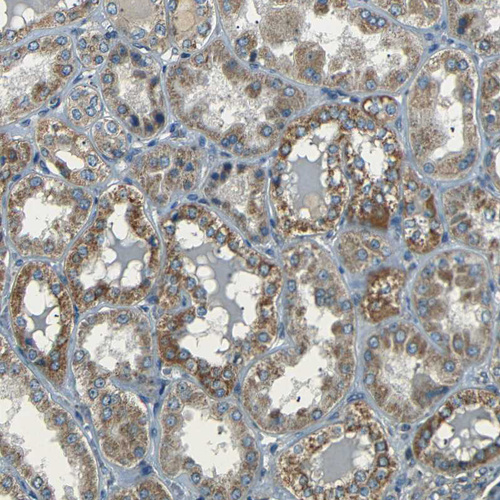

Immunohistochemical staining of human testis shows moderate granular cytoplasm positivity in leydig cells and cells in seminiferous ducts.